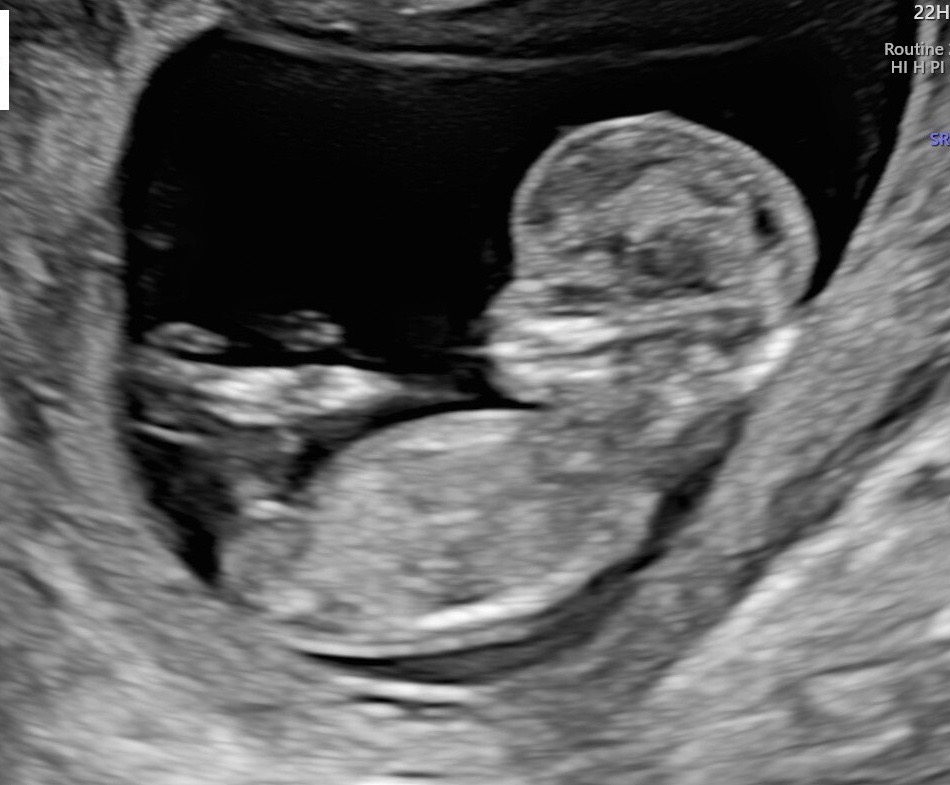

초음파 봐주시던 산파분이 살짝 귀뜸해주시긴 했는데 아직 12주라 정확하지 않다고 하셨어요 제가 볼땐 어쩔땐 딸같다가 아들같고 계속 바뀌는데 다른분들은 어떻게 보이는지 궁금해요!